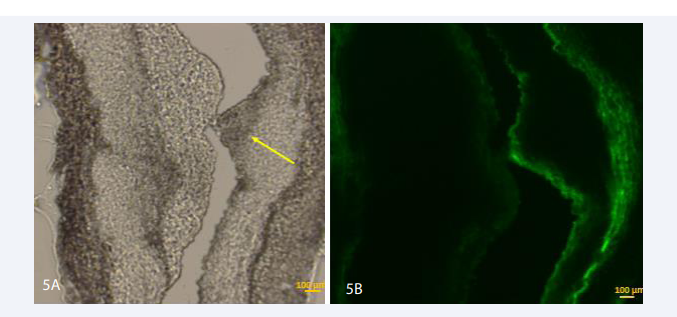

All 17 rabbits had macroscopically signs of plaque in the aorta and iliacs. Introduction of the sheath and balloon through the femoral artery was often difficult due to the small diameter (2.5-3 mm) of the arteries in addition to the calcified aspect of the vessels. In all rabbits microscopy showed plaque in the removed vessel segment (Figure 5A,6A).

Micrographs of sections of the aortoiliac segments from balloon-injured areas in NZ rabbits after 12 weeks of diet, local injection of ICG and contact time of 15  minutes. A: Yellow arrow shows the plaque. B: Fluorescence image: no sign of ICG in the plaque - autofluorescence of the elastic lamina. Magnification 100 x.

Figure 5: Micrographs of sections of the aortoiliac segments from balloon-injured areas in NZ rabbits after 12 weeks of diet, local injection of ICG and contact time of 15 minutes. A: Yellow arrow shows the plaque. B: Fluorescence image: no sign of ICG in the plaque - autofluorescence of the elastic lamina. Magnification 100 x.

Different sets of contact time of ICG with the plaque were used, ranging from 5 to 30 minutes. Table I gives an overview of the experiments with different contact times and subsequent results on microscopy. One rabbit served as a control. In this rabbit a dilatation of the aorta/iliacs was performed without injection of ICG. Microscopy showed autofluorescence of the elastic lamina in all cases (Figure 5B). Consistently a clear fluorescence signal in the atheromatous plaque was seen in rabbits with at least 20 minutes contact time (Figure 6A-6E).

In all rabbits with injection of ICG but a contact time below 20 minutes, no fluorescence signal in the plaque could be detected (Figure 5A,5B). The control rabbit showed atheromatous changes but no fluorescent signal in the plaque (Figure 7A,7B).